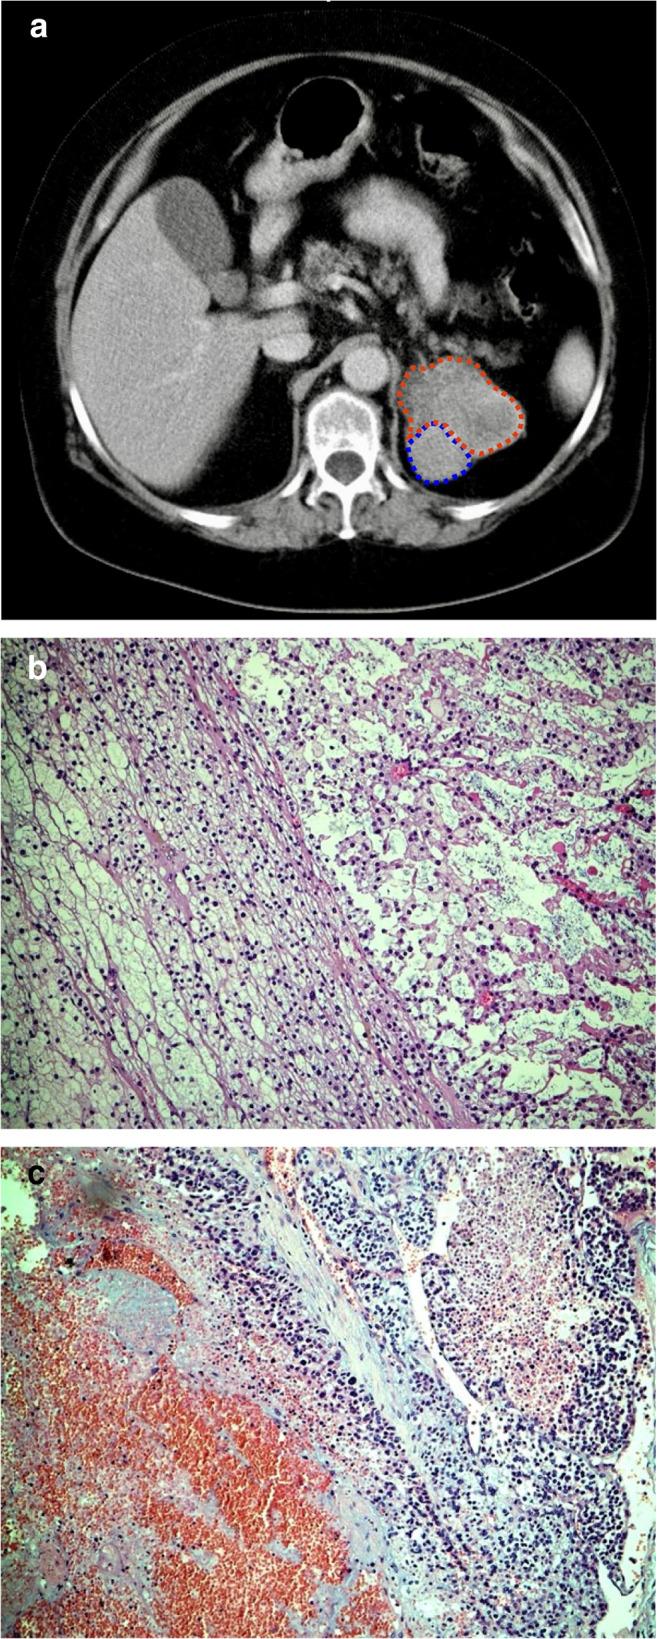

The morphological differentiation between benign and malignant adrenocortical tumors is an ongoing problem in diagnostic pathology. In recent decades the complex scoring systems have been widely used to calculate the probability of malignancy in adrenocortical tumors on the basis of a variety of histomorphological parameters. We herewith present a substantially simplified method to diagnose adrenocortical carcinoma by a single histomorphological parameter on a consecutive series of more than 800 adrenocortical tumors. Between January 2000 and May 2019, altogether 2305 adrenalectomies for of all types of diseases were removed, approximately 98% by minimally invasive approaches. After exclusion of pheochromocytomas, adrenal ganglioneuromas, adrenal metastases, Cushing's disease related specimens, and Conn's adenomas, the present series finally consisted of 837 adrenocortical tumors. All tumors were analyzed by experienced pathologists of a single institution using standard histopathological methods (Hematoxylin-Eosin and Ki67 stained sections). Clinical and histopathologic data were prospectively collected and retrospectively analyzed. Clinically, 385 patients had 420 functioning tumors (FT), and 417 had non-functioning adrenal tumors (NFT). The mean size of FT was 3.8 ± 1.4 cm (range 0.5-16 cm) and for NFT 4.5 ± 1.6 cm (range 1.5-18 cm). Histomorphologically, 32 adrenal tumors were classified as adrenocortical carcinoma (ACC; 3.8%). In all 32 cases (tumor size 9.1 ± 4.0 cm, range 3-18 cm), confluenting tumor necrosis could be demonstrated. The remaining 805 tumors (control group) completely lacked this highly reproducible single morphological feature. Ki67 levels above 10% were found in 31 of 32 ACCs and never in adrenocortical adenomas (ACA). With a mean follow-up of 8.2 years, 24 out of 32 patients primarily diagnosed as ACC developed distant metastases (75.0%), whereas all patients in the control group remained free of local or distant recurrence. We conclude that a single morphological parameter (confluenting tumor necrosis) is sufficient to predict a poor clinical course in adrenocortical tumors. The histomorphological diagnosis of this parameter is straightforward and highly reproducible.

良性与恶性肾上腺皮质肿瘤的形态学鉴别一直是诊断病理学中的难题。近几十年来,复杂的评分系统已被广泛用于根据各种组织形态学参数计算肾上腺皮质肿瘤的恶性概率。在此,我们提出一种大幅简化的方法,通过单一组织形态学参数对连续800多例肾上腺皮质肿瘤进行肾上腺皮质癌的诊断。2000年1月至2019年5月,共进行了2305例各类疾病的肾上腺切除术,约98%通过微创方法进行。排除嗜铬细胞瘤、肾上腺神经节瘤、肾上腺转移瘤、库欣病相关标本和Conn腺瘤后,本系列最终包括837例肾上腺皮质肿瘤。所有肿瘤均由单一机构的经验丰富的病理学家使用标准组织病理学方法(苏木精-伊红染色和Ki67染色切片)进行分析。前瞻性收集临床和组织病理学数据并进行回顾性分析。临床上,385例患者有420例功能性肿瘤(FT),417例有非功能性肾上腺肿瘤(NFT)。FT的平均大小为3.8±1.4 cm(范围0.5 - 16 cm),NFT为4.5±1.6 cm(范围1.5 - 18 cm)。组织形态学上,32例肾上腺肿瘤被分类为肾上腺皮质癌(ACC;3.8%)。在所有32例病例中(肿瘤大小9.1±4.0 cm,范围3 - 18 cm),均可显示融合性肿瘤坏死。其余805例肿瘤(对照组)完全缺乏这种高度可重复的单一形态学特征。32例ACC中有31例Ki67水平高于10%,而肾上腺皮质腺瘤(ACA)中从未发现。平均随访8.2年,最初诊断为ACC的32例患者中有24例发生远处转移(75.0%),而对照组所有患者均无局部或远处复发。我们得出结论,单一形态学参数(融合性肿瘤坏死)足以预测肾上腺皮质肿瘤的不良临床病程。该参数的组织形态学诊断简单且高度可重复。